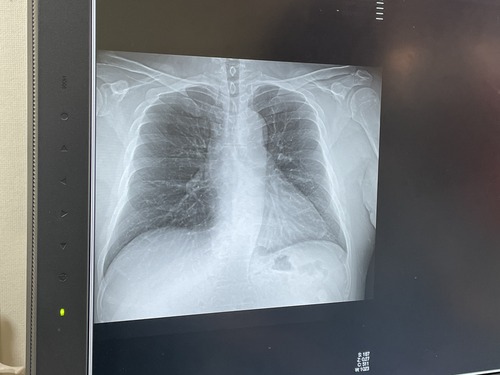

さて、翌朝、電話をしたのだが、いよいよ声が何言ってるか分からん状態。こっちは一所懸命、声を張り上げているのだが、電話越しには雑音以外に聞こえなかったらしい。埒が明かないので、嫁はんを叩き起こして電話させ、1000時に検査を受ける事になった。検査の方法は、23年の9月の時と同様、車の窓越しに検査棒を鼻に突っ込まれるやり方で、結果はまさかのコロナ陽性。インフルはAもBも陰性という事だった。前回同様に、ゾコーバとカロナール、そして鼻や喉の薬を処方された。違うのは、前回はゾコーバは政府持ちだったが、今回は自分持ちで、保険適用でも1.6万円した。